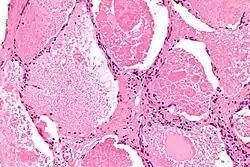

![]() صورة مجهرية للداء البروتيني السنخي الرئوي، تظهر الفراغات الهوائية مملوءة بكثافات موضعية تدعى بـ الأجسام الكثيفة. صبغة الهيماتوكسيلين واليوزين. صورة مجهرية للداء البروتيني السنخي الرئوي، تظهر الفراغات الهوائية مملوءة بكثافات موضعية تدعى بـ الأجسام الكثيفة. صبغة الهيماتوكسيلين واليوزين. | |

يتم الحصول على غسالة رئوية أو أنسجة لتحليل التشريح المرضي باستخدام غسل القصبات والأسناخ و/ أو خزعة الرئة.[27] تُظهر نتائج الخزعة المميزة امتلاء الحويصلات الهوائية (وأحياناً القصبات الهوائية الانتهائية) بمادة غير متجانسة محبة للحمض، والتي تتلون بشدة على صبغة PAS. في حين تبقى الحويصلات الهوائية المحيطة والخلايا الرئوية الخلالية طبيعية نسبياً.[28] يُظهر الفحص المجهري الإلكتروني للعينة جسيمات صُفاحية تمثل الفاعل بالسطح.[29] يتداخل التشخيص مع أمراض ذات نتائج مماثلة مجهرياً هي الالتهاب الرئوي بالمتكيسة الرئوية الجؤجؤية.[12]